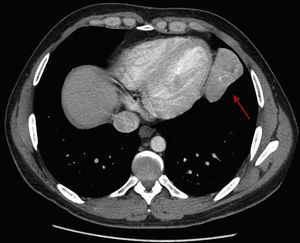

Se expone el caso de un varón de 35 años, sin antecedentes personales de interés, que presenta tos, fiebre y expectoración amarillenta de una semana de evolución, con radiografía de tórax en la que se aprecia una opacidad pulmonar en el lóbulo inferior izquierdo (fig. 1). Se le pauta tratamiento antibiótico, con una evolución clínica favorable. Sin embargo, en las sucesivas radiografías posteriores dicha opacidad apenas se modifica. Ante la sospecha de enfermedad tumoral subyacente, se realiza una fibrobroncoscopia, que no muestra hallazgos de significado patológico. Finalmente al paciente se le realiza una tomografía axial computarizada de tórax para filiar la lesión (fig. 2), encontrando una masa heterogénea en el lóbulo inferior izquierdo que recibe aporte vascular arterial desde el tronco celíaco y drenaje venoso sistémico a la vena cava inferior. Estos hallazgos son compatibles con un secuestro pulmonar extralobar.